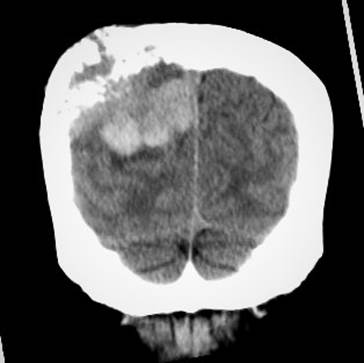

Ilustración 9 Metástasis cerebral con destrucción occipital.

Fuente: Hospital de Especialidades Guayaquil “Doctor Abel Gilbert Pontón”.

Autor: Dr. Fernando Moncayo A.

Paciente de 68 años de edad, que ingresa referida de otra institución por presentar más tumoral en región occipital derecha de gran tamaño dura muy adherida, dolorosa con circulación colateral; paciente desorientada en tiempo y espacio, irritable y poco colaborativa, en algunas ocasiones ha presentado convulsiones tónico clónicas. Además, presenta masa cervical voluminosa, a nivel tiroidea, dura, adherida a estructura aéreas y vasculares.

Se toma biopsia con aguja gruesa de lesión tumoral cervical y tumoración occipital encontrando carcinoma papilar variante oncocitica.  Paciente fue tratada por el departamento de oncología clínica en forma paliativa y con Sorafenib por no haber mejoría con radio-yodo.